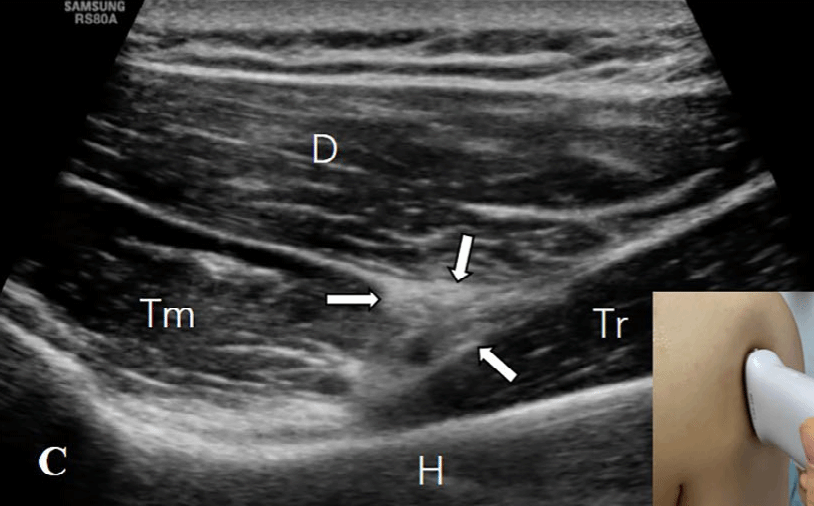

探头的位置根据三个解剖标志来确定:四边孔、肩胛下肌的前方和腋动脉的后方。1)四边孔:由上方的小圆肌、下方的大圆肌、内侧的肱三头肌长头和肱外侧的骨外科颈构成。在评估这个区域时,患者取坐位,肩部处于中立位置。探头沿纵向放置在肩胛骨的外缘和肩胛骨下角下方,以显示冈下肌和小圆肌的短轴切面(图2A)。探头沿着矢状面向外侧移动,直到出现肱三头肌长头腱(图2B)。在这一切面上,小圆肌位于肱三头肌长头的头侧和浅方,大圆肌位于足侧和深方。探头继续向外侧移动,直到出现肱骨干(图2C)。在此切面上,腋神经(AN)和旋肱后动脉位于由头侧的小圆肌(Tm)、足侧的肱三头肌长头(Tr)、浅方的三角肌(D)和深方的肱骨干围成的空间内。通过调整探头,可以更清楚地显示神经血管束(图2D)。

图2C:探头继续向外侧移动,直到出现肱骨干(图1C)。在此切面上,腋神经(AN)和旋肱后动脉(白色箭之间)位于由头侧的小圆肌(Tm)、足侧的肱三头肌长头(Tr)、浅方的三角肌(D)和深方的肱骨干围成的空间内。